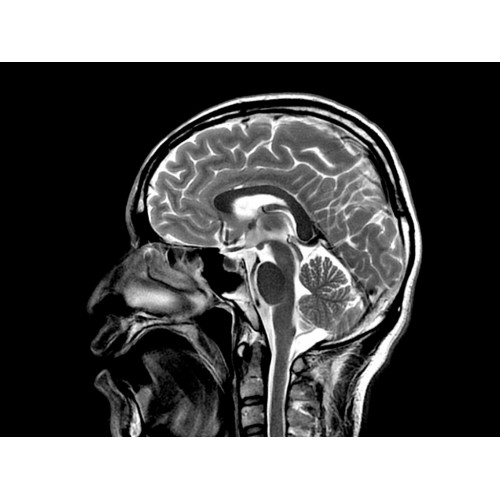

МРТ аппарат GE Optima MR450w 1.5T

МР-томограф с широким туннелем Optima MR450w является настоящей рабочей лошадкой и может эффективно обслуживать большее число пациентов. Томограф обеспечивает одновременно удобство пациента, продуктивность работы, отличное качество изображения. В этой МРТ-системе инженерам компании удалось без компромиссов совместить необходимый объем перемещения с удивительно высоким качеством изображения.

Благодаря принципиально новым технологиям мы расширили возможности МР-томографов с широкими туннелями, совместив непревзойденное качество изображений с высокой производительностью при широком — 50 см — поле зрения.

МР-томограф Optima MR450w позволяет получать изображения исключительно высокого качества, которые помогают установить диагноз. Чтобы удовлетворить ожидания клиентов в отношении высокого качества, в МР-томографе Optima MR450w были сохранены дополнительные возможности платформы Discoverу, привнесшие в его работу универсальность и мощь.

• Цифровой РЧ-приемник OpTix — эксклюзивная оптическая РЧ-система увеличивает четкость сигнала и его интенсивность, формируя чистые и резкие изображения.

• РЧ-катушки, оптимизированные для исследования конкретных участков тела — элементы катушек высокой плотности располагаются вокруг исследуемых участков тела и при необходимости обеспечивают расширенный охват и оптимальное качество изображений при каждой процедуре.

• Широкое поле зрения — поле зрения шириной 50 см позволяет охватывать крупные анатомические области за меньшее число сканов.